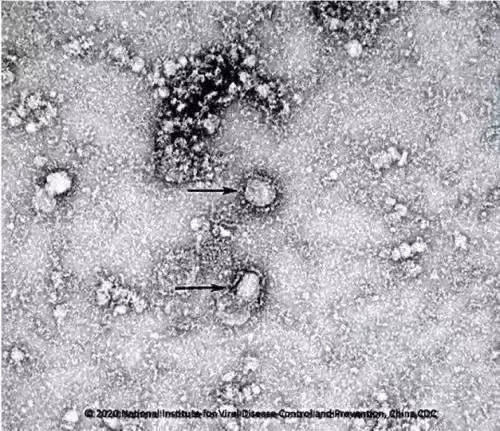

具体到这次新冠病毒肺炎,中国科学家们在最早发病的几十位患者体内,利用电子显微镜、RT-PCR和高通量DNA测序等方法检测到了这种病毒的存在(科赫法则1)[1,2];也成功分离出了这种病毒颗粒并且证明了它们在培养皿里仍然能够侵染人上皮细胞(科赫法则2)[1]。当然,因为目前人们还没有新冠病毒的动物模型。无法直接验证科赫法则3和4,但是科学家们也证明了只要在老鼠细胞里转入一个人类的ACE2蛋白——猜测中的新冠病毒受体,病毒就可以顺利侵染这些老鼠细胞。这个结论至少是部分支持了科赫法则3和4的成立[3]。

浙江省疾控中心新型冠状病毒检测团队成功分离的新型冠状病毒毒株